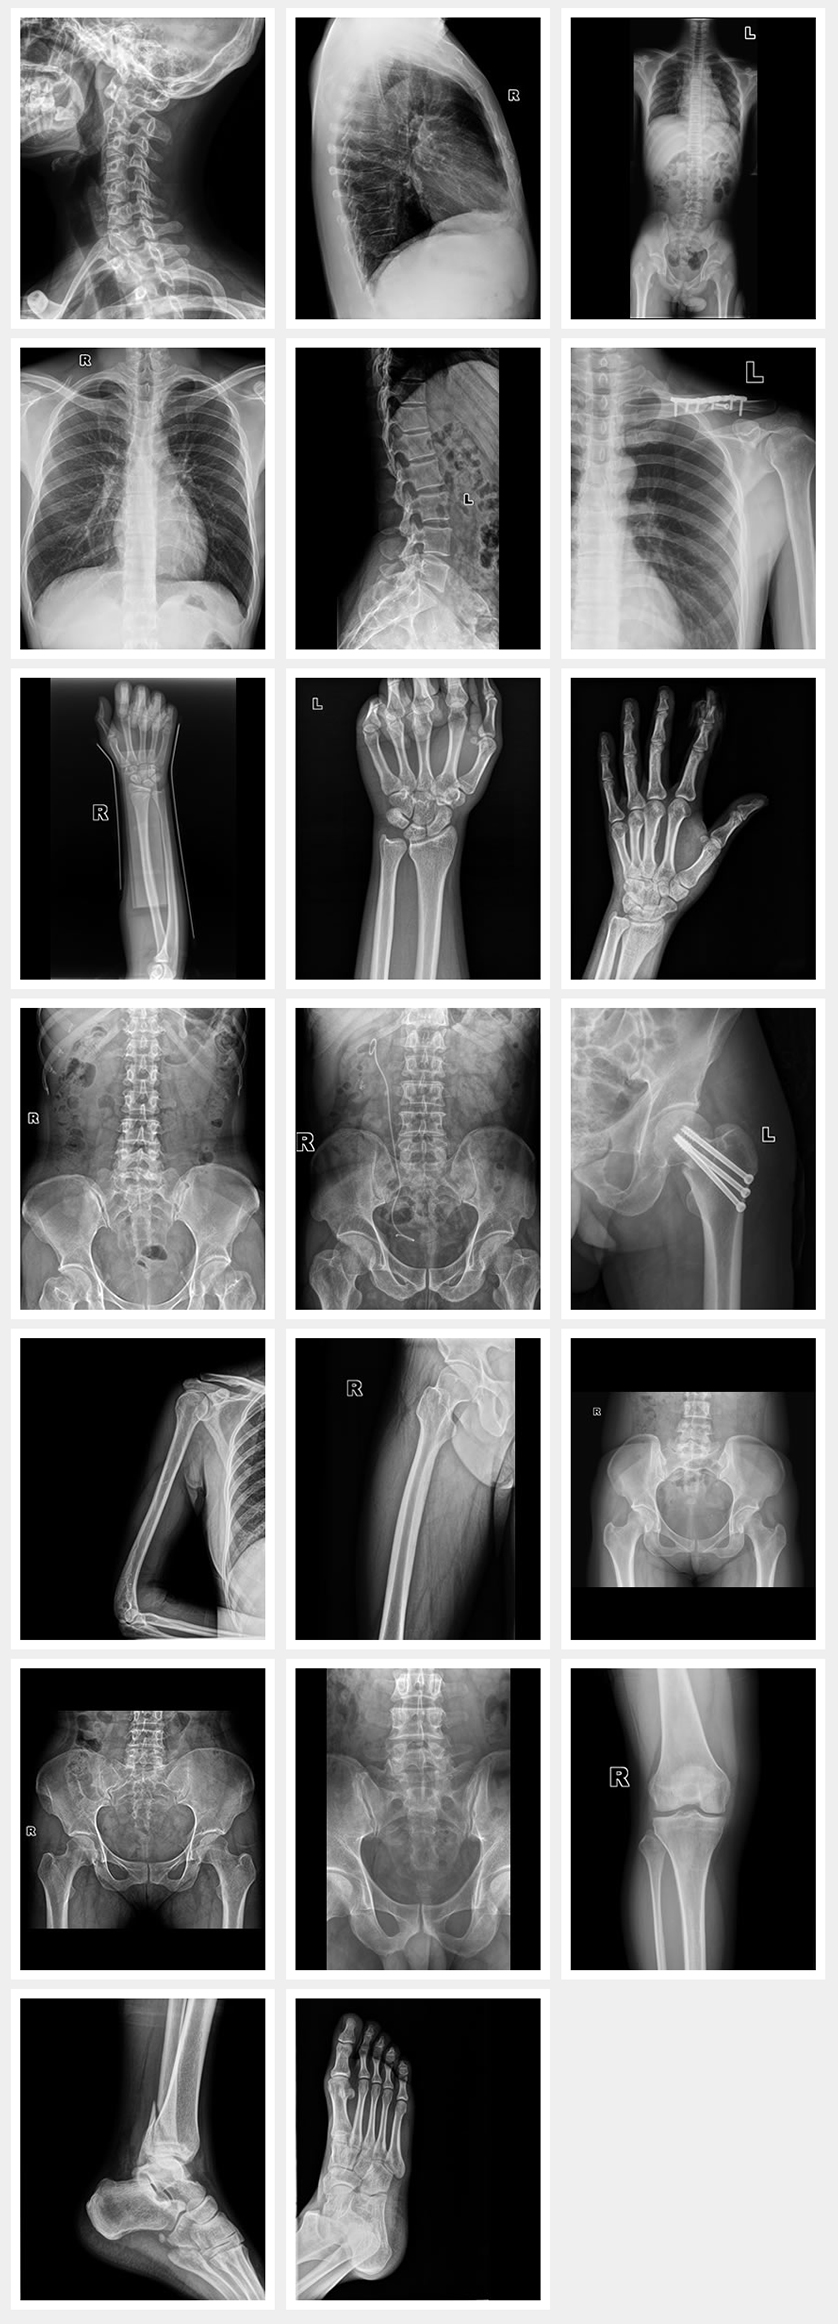

Applications

Images cliniques